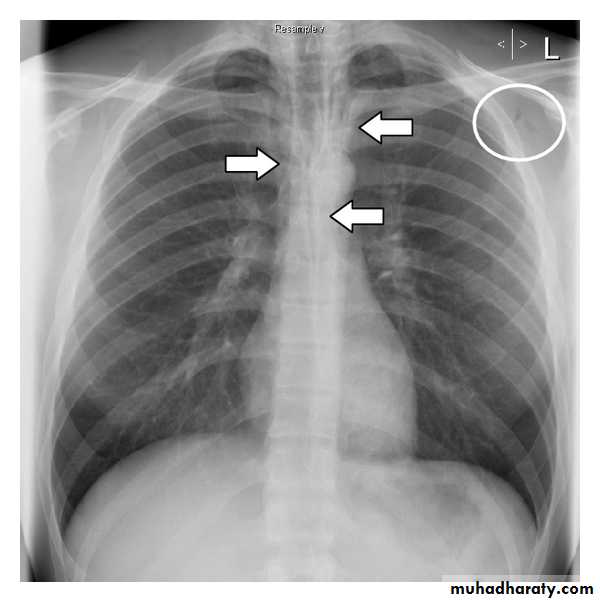

Left upper lobe collapse has distinctive features but can be challenging to identify on chest radiographs by the uninitiated.

Radiographic features

The left upper lobe collapses anteriorly becoming a thin sheet of tissue apposed to the anterior chest wall, and appears as a hazy or veiling opacity extending out from the hilum and fading out inferiorly . It thus reverses the normal slight increase in radiographic density seen as you move down the lung (due to increased thickness of the chest soft tissues).

Parts of the normal cardiomediastinal contour may also be obliterated where the left upper lobe, particularly the lingula abut the left heart border. The anterior parts of the aortic arch are also often obliterated from view.

In some cases the hyperexpanded superior segment of the left lower lobe insinuates itself between the left upper lobe and the superior mediastinum, sharply silhouetting the aortic arch and resulting in a lucency medially. This is known as the luftsichel sign.

The left hilum is also drawn upwards, resulting in an almost horizontal course of the left main bronchus and vertical course of the left lower lobe bronchus.

Non-specific signs indicating left sided atelectasis will also be present, including:

elevation of the hemidiaphragm

'peaked' or 'tented' hemidiaphragm: juxtaphrenic peak sign

crowding of the left sided ribs

shift of the mediastinum to the left

On lateral projections the left lower lobe is hyperexpanded and the oblique fissure displaced anteriorly. There is associated increase in the retrosternal opacity.